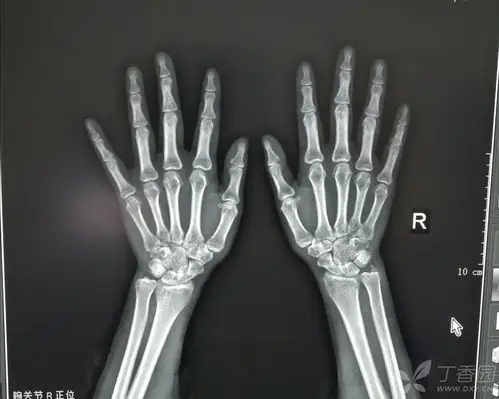

右尺骨茎突撕脱骨折?